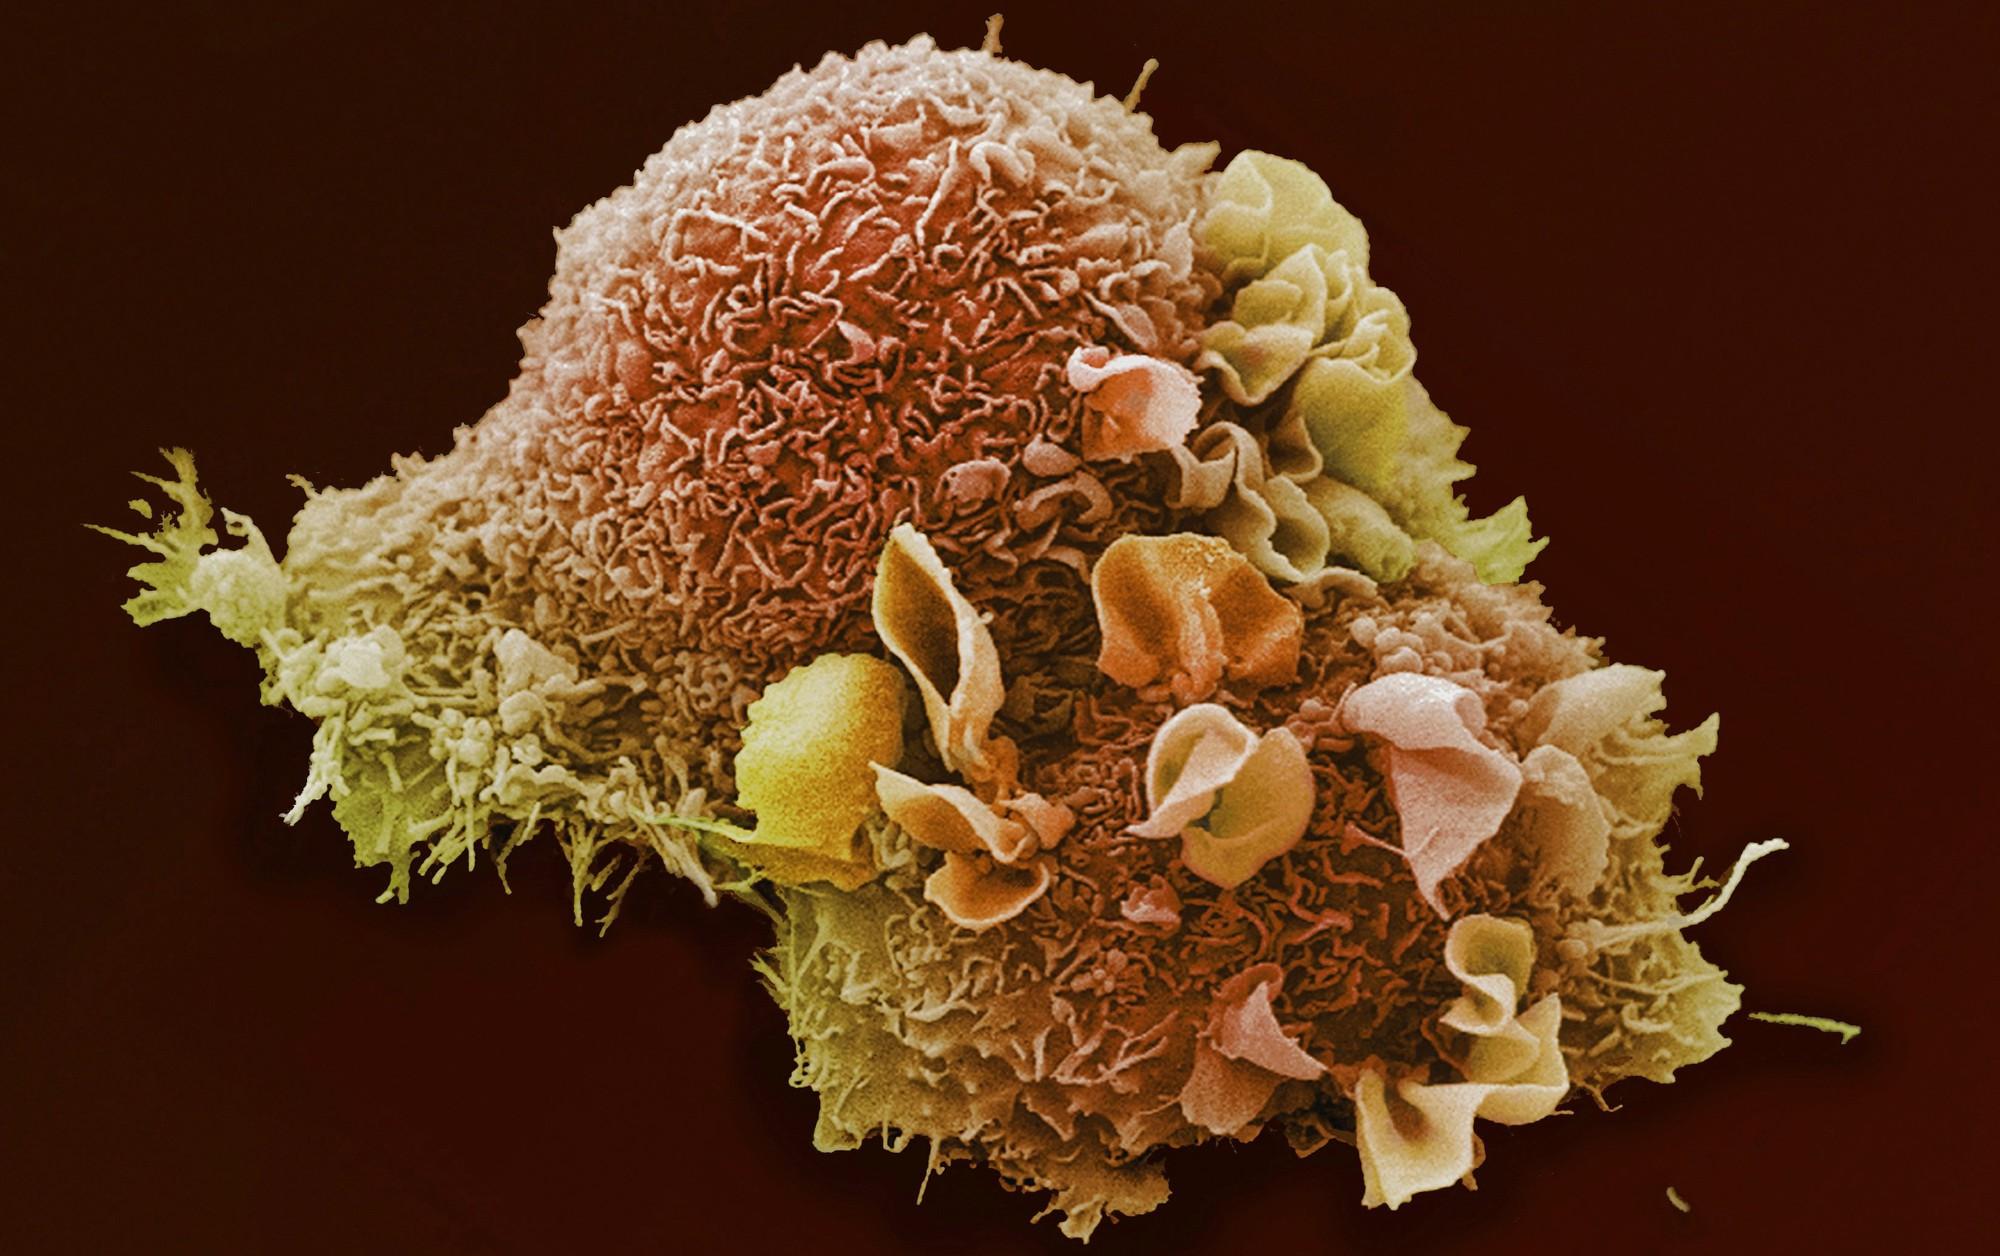

Раковая шишка – это заболевание, которое поражает кожу и слизистые оболочки. Она может возникнуть в различных частях тела и иметь различные внешние проявления. В данной статье мы представляем вам многочисленные фотографии раковых шишек, чтобы вы могли узнать, как они выглядят.